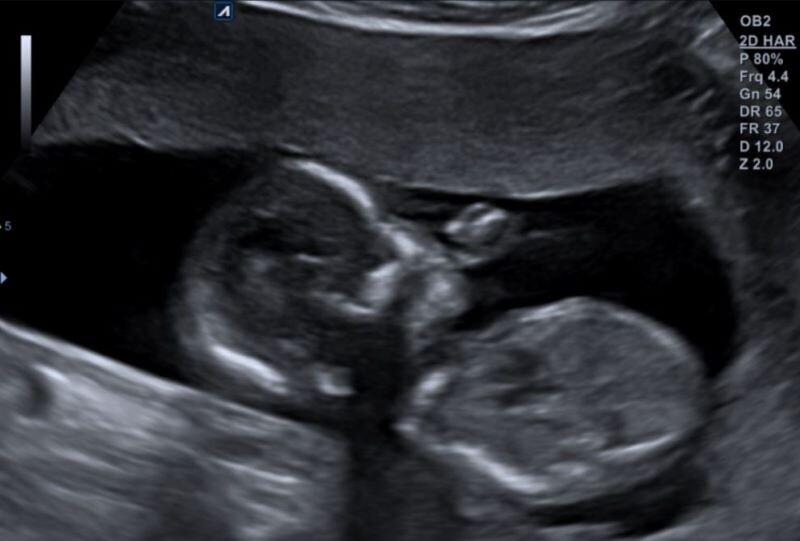

Hier een echo foto van onze baby die lekker aan het duimen is ❤.